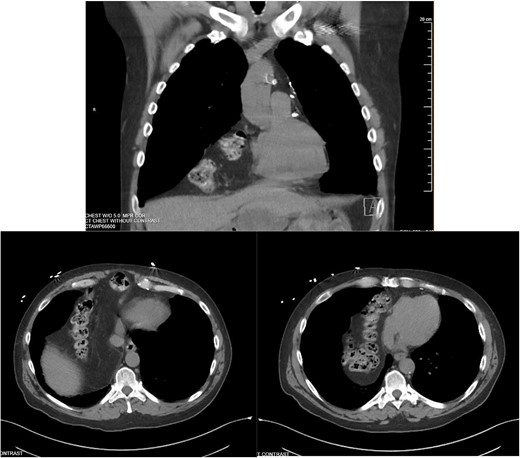

A 55-year-old male underwent lung cancer screening with a chest CT scan (Fig. 1) and was incidentally found to have an anterior diaphragmatic hernia just inferior to the sternum.